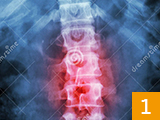

治疗前后炎症对比图/ Inflammation contrast

• 治疗前

• 治疗后